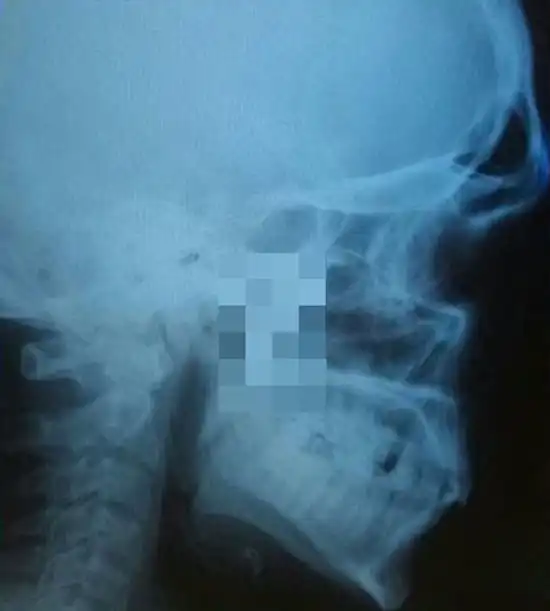

Нередко врачи вынуждены извлекать из тел людей самые необычные посторонние предметы, которые не должны были там находиться. В данном случае из мягкого нёба мужчины достали лезвие небольшого ножа, вошедшего под скуловой дугой во время драки. Случилось это за месяц до обращения за медицинской помощью, а беспокоиться пациент начал только потому, что нащупал нечто постороннее в нёбе.